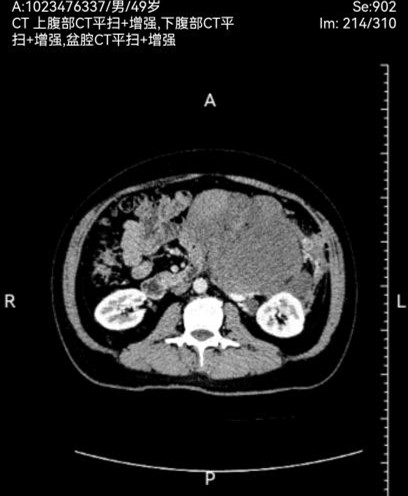

此次两名患者均因“腹部胀痛、包块及进食受限”入院,经增强CT三维重建及磁共振等检查,确诊为腹膜后巨大肿瘤。一例左侧腹膜后肿瘤,长径达30cm,重约4.8kg,紧贴腹主动脉及腹腔干,侵犯脾动脉根部及胰体尾、脾门、右肾及右肾上腺,与结肠系膜粘连紧密,挤压胃肠道引发不全梗阻;另一例右侧腹膜后肿瘤,长径40cm,重约3.2kg,侵犯结肠系膜根部血管,血供丰富,同时挤压肝门及十二指肠,存在右肾蒂损伤风险。